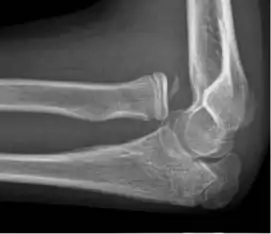

- Elbow: Posterior dislocation, 90% of all elbow dislocations[29]